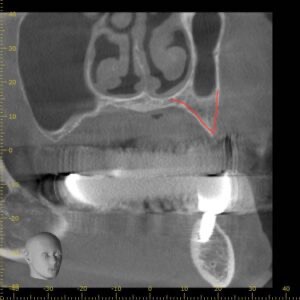

横から見たCT画像です。

上顎の上方には副鼻腔(上顎洞)と呼ばれる、鼻とつながる空洞が存在します。

下の赤線で囲まれた部分です。

この部分にインプラントが飛び出してしまうと鼻に炎症を起こす可能性があるため、その下の骨の内部で留める必要があります。

今回の画像をみるとわかりますが、骨が極端に少ない状態です。

どのサイズのインプラントが適切か判断するため

CT画像を使用し、インプラントのシュミレーションを行います。

後ろのインプラントが副鼻腔に飛び出してしまうのがわかると思います。